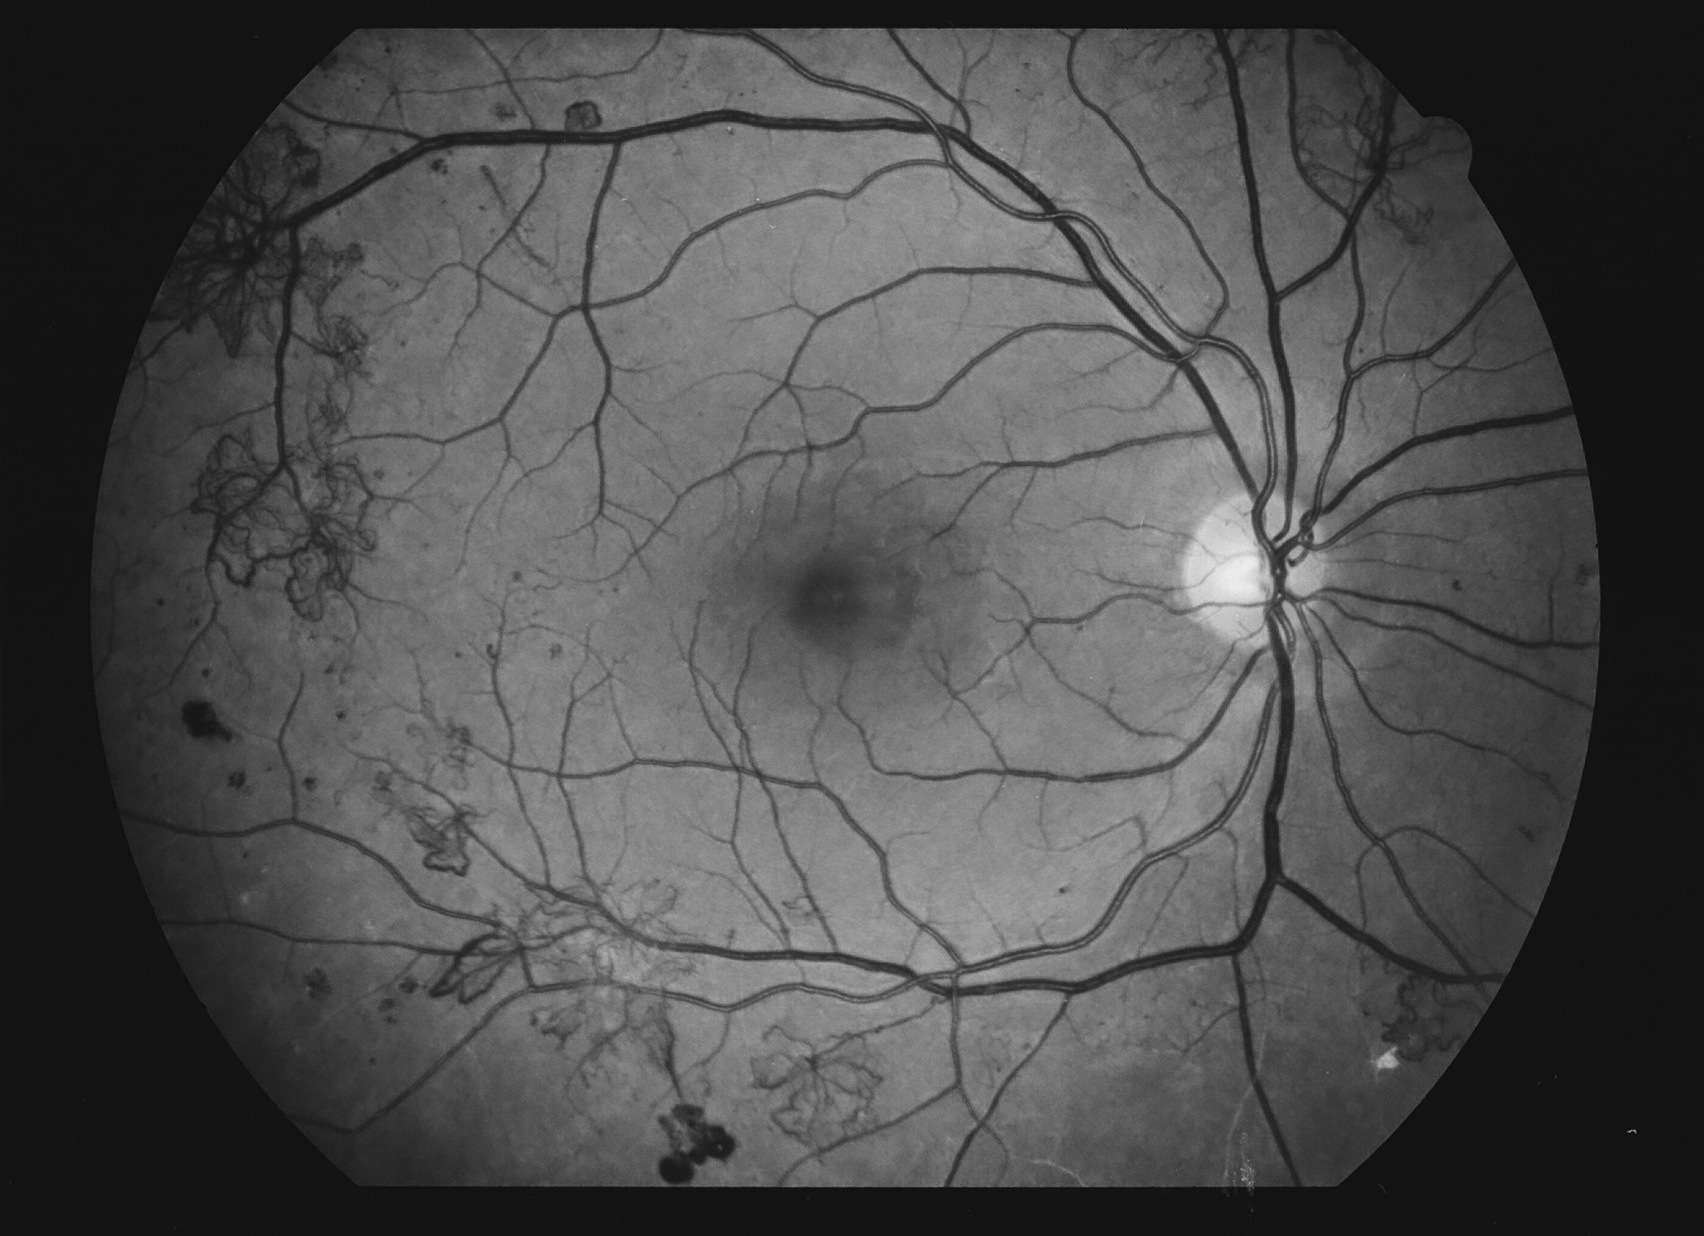

Kuva 14.

Diabetes, proliferatiivinen retinopatia, vasen silmä. Mikroaneurysmia, vuotoja, silmukoita laskimoissa eli laskimolenkkejä ja uudissuonia.

Kuva 15.

Diabetes, proliferatiivinen retinopatia, oikea silmä. Mikroaneurysmia, vuotoja, venopatiaa ja näköhermon keskikuopan reunalla uudissuonikasvua.